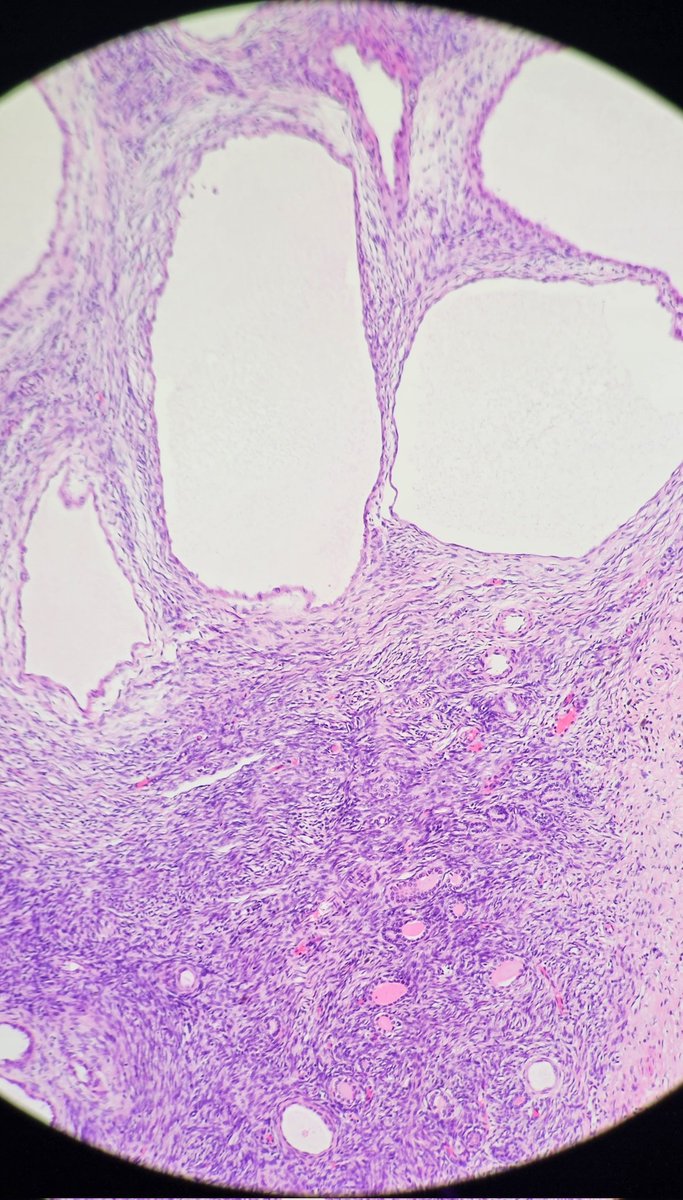

Young female with untreated HIV presents with GI bleeding and adenopathy. Which stain or stains would be the most useful to determine the cause of her symptoms? Pictures: Colon Bx, Mesenteric lymph node, Omentum #GIpath #pathology